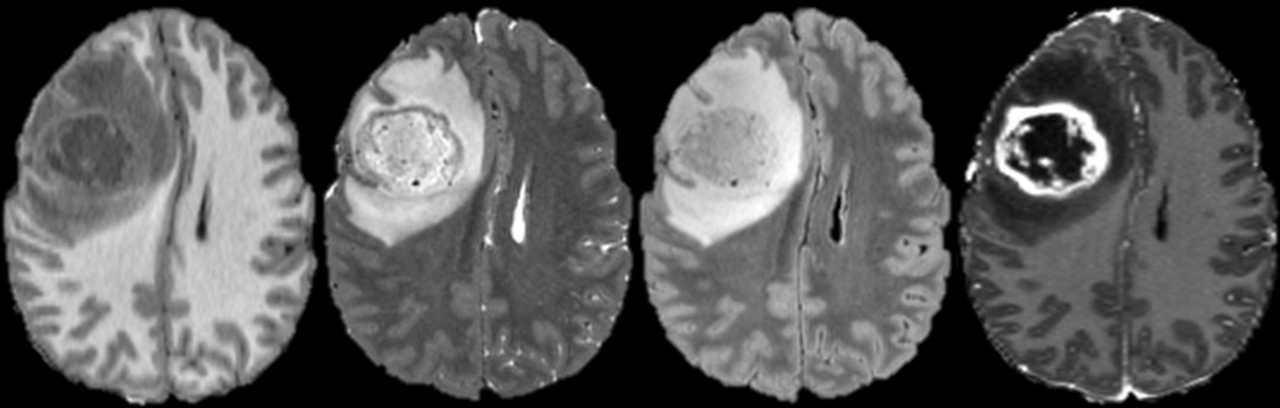

Receiver operating characteristic (ROC) curves for the 4 best predicted glioblastoma genetic biomarkers: isocitrate dehydrogenase mutations (IDH), ATRX mutations (ATRX), chromosome 7 & 10 aneuploidy (Chromosome 7/10), and CDKN2 family gene loss (CDKN2). Blue lines represent the average ROC and shaded gray areas represent the ± 1 standard deviation interval. Red dotted lines indicate random chance (true positive rate = false positive rate). The average ROC area under the curve (AUC) ± 1 standard deviation is displayed on each plot.